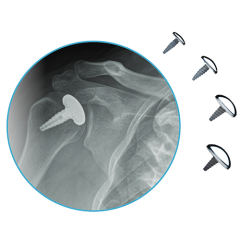

Explore our broad range ofOrthopedic Products

We are dedicated to improving the quality of life of patients suffering with bone and joint problems by delivering the latest medical devices that are proven to be effective and backed by scientific studies and research

• Surgical Devices